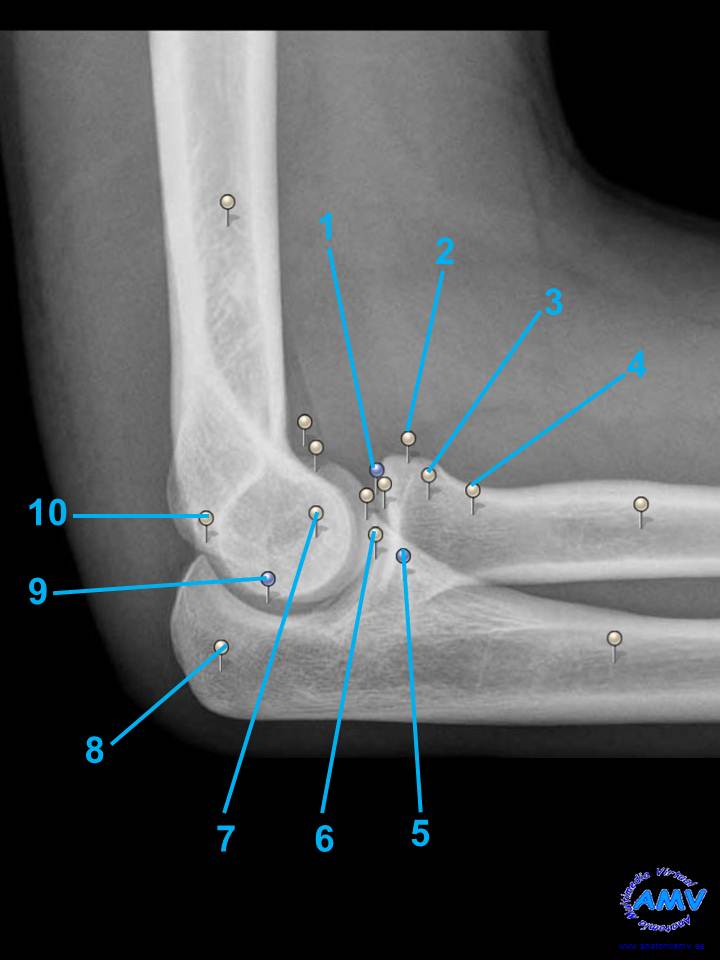

rx_ms_08.jpgIndique que estructura se señala con el número correspondiente:

El nº 1 señala .

El nº 2 señala .

El nº 3 señala .

El nº 4 señala .

El nº 5 señala .

El nº 6 señala .

El nº 7 señala .

El nº 8 señala .

El nº 9 señala .

El nº 10 señala .